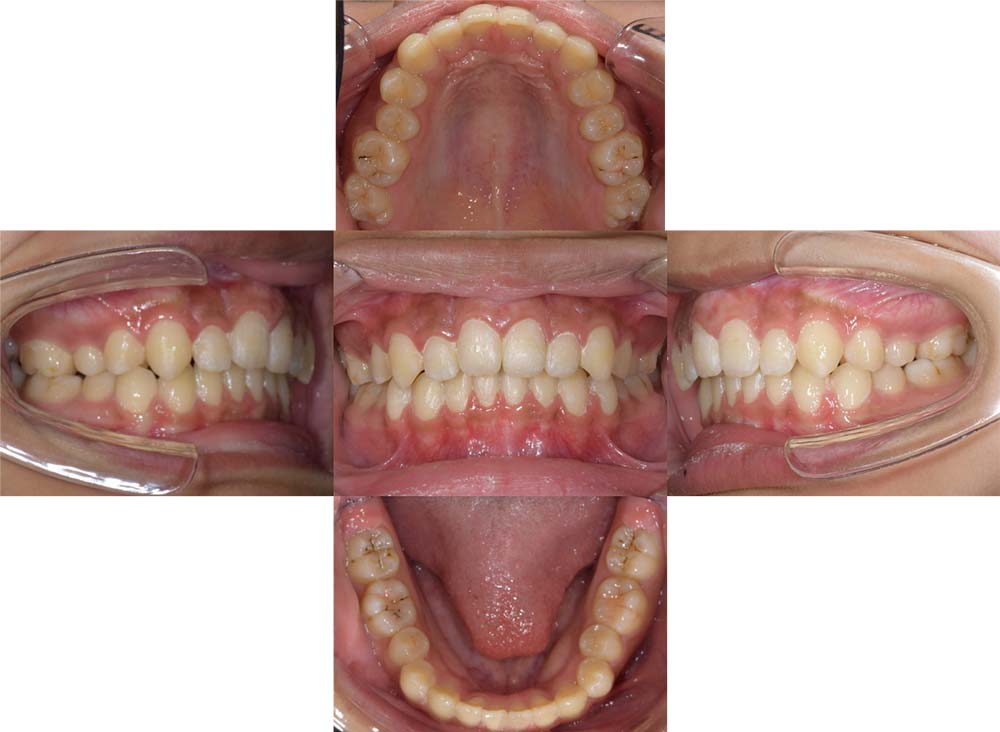

症例02

| 主訴 | 下あご顎が出ている。曲がっている。 |

| 診断名あるいは主な症状 | 反対咬合、非対称、空隙歯列、過蓋咬合 |

| 年齢/性別 | 19歳・女性 |

| 矯正ステージ | 大人の矯正治療 |

| 治療方法 | ワイヤー矯正、顎矯正手術の施行 |

| 抜歯部位/抜歯有無 | 非抜歯 |

| 治療内容 | 上下顎歯列を並べた後に顎矯正手術の施行。 |

| 費用 | 保険治療 |

| 治療期間 | 3年2ヶ月 |

| 主なリスク・副作用 | 痛み、歯根吸収、歯肉退縮、虫歯、後戻り |